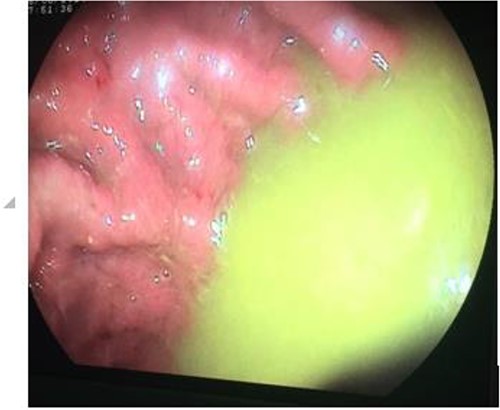

Laboratory tests found anemia (9 g/dl), hypoalbuminemia (26.1 g/dl) and hypocholesterolemia (2.6 mmol/L). Upper endoscopy showed the evidence of fecal liquid in gastric cavity (Fig. 1). Colonoscopy showed two structures with a luminal appearance at the distal transverse colon. Upon advancing the colonoscope through these structures, intestinal mucosa were identified and histopathological examination of biopsies showed jejunal and duodenal mucosa.

Upper endoscopy showing gastric stasis and fecal liquid in gastric cavity.